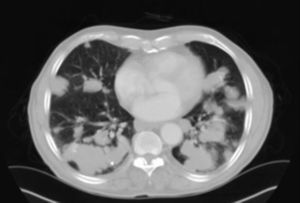

An 80-year-old man, a former smoker, presented with a few months’ history of dyspnea and systemic signs (asthenia, anorexia and loss of weight). Physical examination and laboratory tests results did not reveal any significant changes. Chest X-ray showed multiple disperse nodular lesions in both lung fields. Chest and abdominal computed tomography (CT) found disperse nodular pulmonary lesions with lobulated borders and no calcifications, in both lungs (Fig. 1). No microorganisms or malignant cells were identified in bronchoscopy specimens. PET-CT results suggested that some of the lesions in both lungs had significantly higher affinity for FDG than others, and there were no lesions with increased uptake in any other part of the body. Lung function tests showed moderate airway obstruction. Transthoracic and transbronchial biopsies showed amorphous amyloid-type cells. Two years after diagnosis, the patient remains in good clinical condition under treatment with inhaled long-acting beta-antagonist bronchodilator and corticosteroid.

From a radiological point of view, primary nodular parenchymal pulmonary amyloidosis occurs in the form of single or multiple nodules in any lobe, and must be taken into account in the differential diagnosis of primary or metastatic pulmonary malignancies, pulmonary tuberculosis, pulmonary sarcoidosis, and connective tissue diseases.2 Nodules are generally peripheral and subpleural and 4 typical features are observed on CT: well-defined lobulated borders, calcification that is often central or forms in an irregular pattern within the nodule, multiple shapes and sizes, and slow growth, often over years, with no remission.3